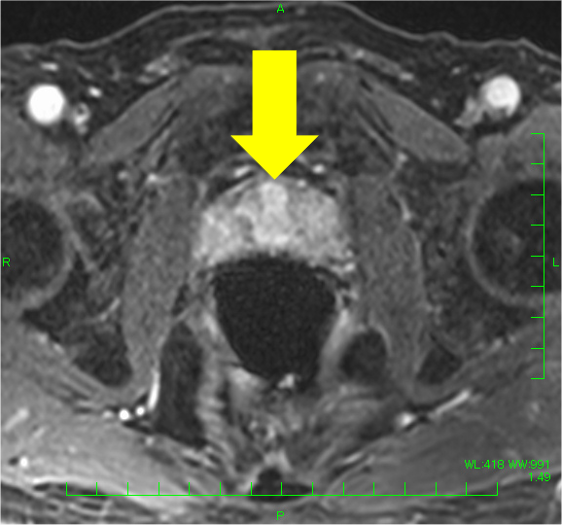

検診でPSA 4.9と上昇があり、MRIが施行された。左移行域に14mmの病変を認め、T2強調像で低信号(PI-RADS v2.1スコア4)、拡散強調像で高信号・Appar-ent Diffusion Coefficient(ADC)低下(スコア4)、ダイナミックで早期濃染を示し、PI-RADS v2.1でカテゴリー4と判定され前立腺癌が疑われた。一方、辺縁域はT2強調像で不均一低信号を呈したが、結節様の拡散強調像での強い高信号、ADC低下はなく、ダイナミックMRIでも結節様の早期濃染はなく、びまん性遷延性の染まりがみられたことから炎症性変化と判断した。生検が行われ、癌の診断であった。その後、ロボット支援下根治的前立腺摘除術が施行され、MRIと一致した前立腺癌の診断を得た(Gleason score 4+3=7, pT2N0)。

本症例では、左移行域腹側の病変(14mm、T2強調像:低信号(スコア4)、拡散強調像:高信号・ADC:低下(スコア4)、ダイナミック:早期濃染: PI-RADS v2.1カテゴリー4)は、前立腺癌の判定が容易であった。一方、辺縁域はT2強調像でびまん性に不均一な低信号を呈し、癌の評価が難しい方であった。左辺縁域に小結節様のT2強調像にて低信号がみられ、拡散強調像やADCの所見は明瞭でなく癌の可能性は低いと考えたが、T2強調像での信号が明瞭で、癌を否定してよいのか悩ましい。本症例では、ダイナミックMRIも施行しており、左移行域腹側病変は早期濃染―washout パターンを呈したが、左辺縁域の小結節に早期濃染はなく、両側辺縁域とも遷延性の染まりを認めたため、辺縁域に癌はなく、両側辺縁域に炎症性変化があると断定できた。病理的にも、MRIで指摘した病変部のみ癌が同定され、その他の領域に癌はなかった。